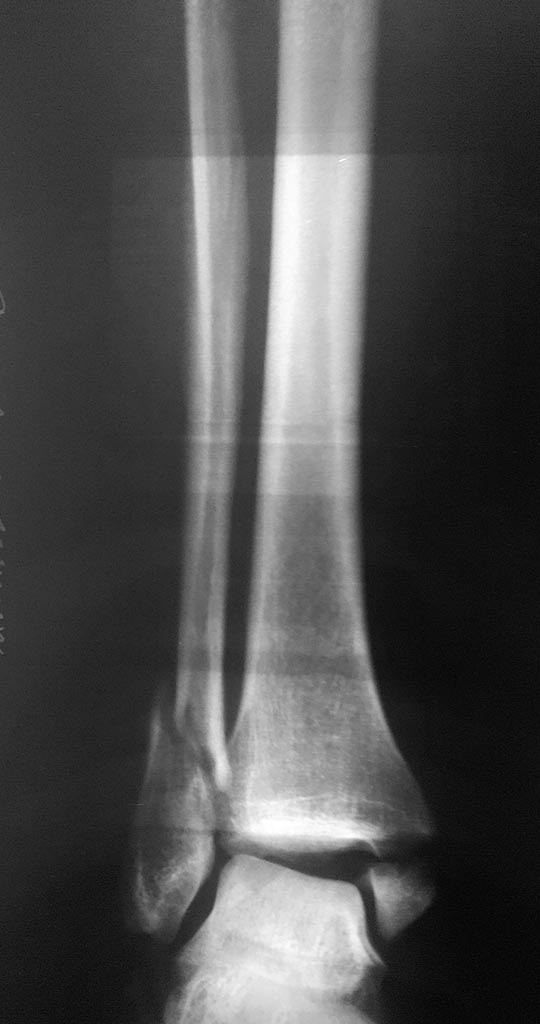

[Ortho] Лодыжки - подвывих стопы?

Имя     : 2.jpg

Url     : http://weborto.net:8080/pipermail/ortho/attachments/20180225/ed17c2c1/attachment-0003.jpg